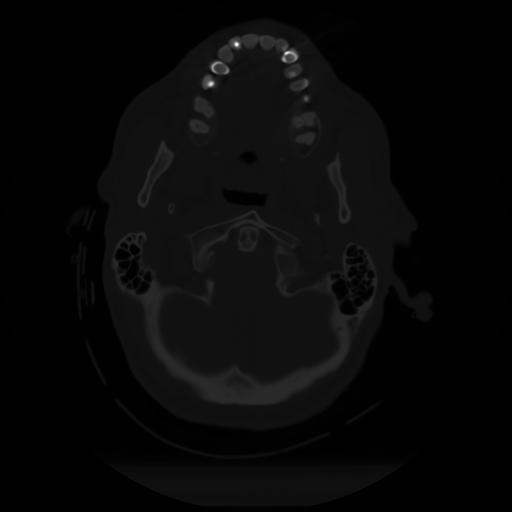

10 P.BLANDAS,,Axial,2.0,P.BLANDAS,,